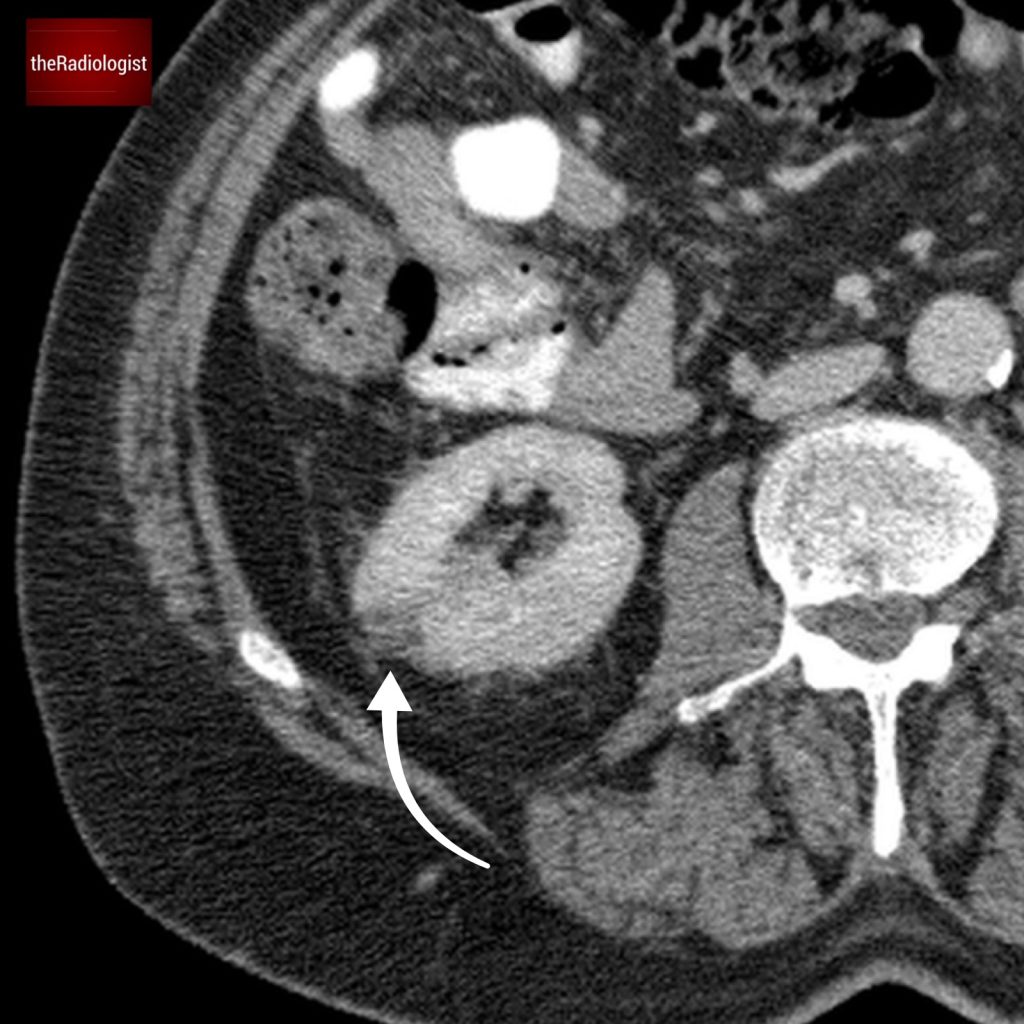

If we look at the psoas muscles on this scan below we can see there is some asymmetry . The right psoas is larger than the left and we’ve lost some of the fat planes within the muscle.

Compare the psoas muscles side by side. The right sided psoas muscle appears expanded with a loss of its normal fat planes.

Also as we scroll down we can see there is fat stranding surrounding the psoas muscle extending into the pelvis.

There is fat stranding surrounding the psoas extending into the pelvis.